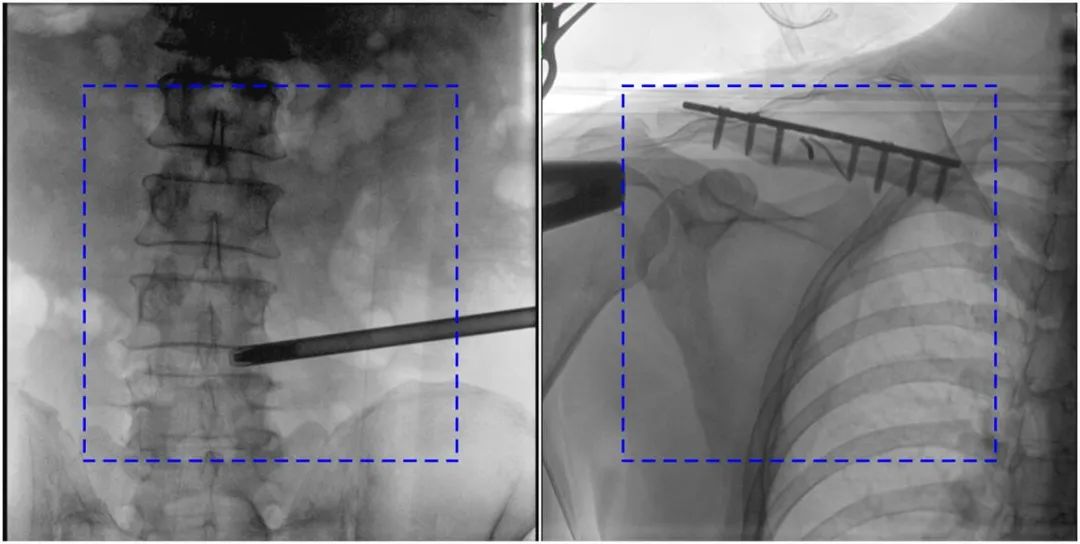

PLX119C臨床圖像與傳統(tǒng)圖像對(duì)比

注:藍(lán)色虛線內(nèi)為傳統(tǒng)21CM×21CM平板的成像區(qū)域。